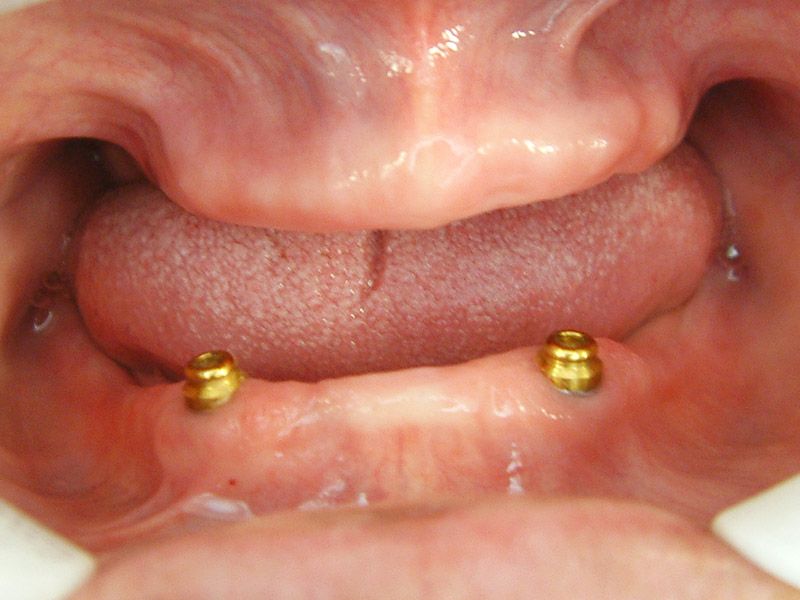

上:半口活動義齒 下:兩顆植體覆蓋式活動義齒 ft.林錫奎醫師

上:半口活動義齒 下:兩顆植體覆蓋式活動義齒

治療前